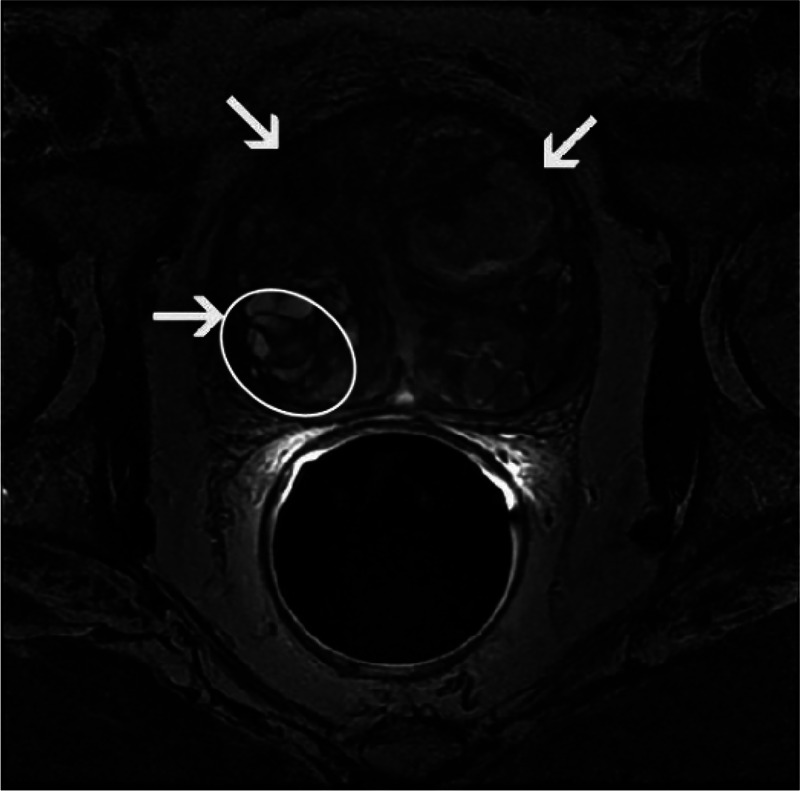

良性前列腺增生常见于老年男性,手术是主要治疗方法。前列腺增生结节,尤其是包埋性包膜增生结节的处理,对于减少术后并发症的发生率和减少重复手术的需要至关重要。我们就前列腺增生结节的来源、结节与前列腺手术包膜的关系、各种手术方式治疗增生结节的优缺点以及手术对术后并发症发生率的影响进行综述。此外,我们也将分享我们使用铥激光切除前列腺内埋包膜增生结节的治疗经验。我们希望医生在临床实践中重视前列腺手术中浸润性囊膜增生结节的处理。

Benign prostatic hyperplasia is commonly observed in older men, and surgery is the primary treatment. Management of prostatic hyperplasia nodules, especially embedded capsular hyperplasia nodules, is crucial for reducing the incidence of postoperative complications and the need for repeat surgery. We summarize the sources of prostatic hyperplasia nodules, relationship between the nodules and the surgical capsule of the prostate, advantages and disadvantages of various surgical procedures for hyperplasia nodules, and impact of surgery on the incidence of postoperative complications. Additionally, we share our experience with the management of embedded capsular hyperplasia nodules using thulium laser enucleation of the prostate. We hope that doctors will pay attention to the management of embedded capsular hyperplasia nodules during prostate surgery in their clinical practice.